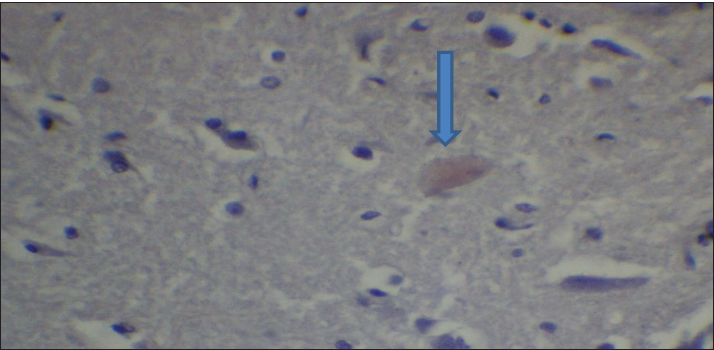

Fig. 2. Effect of gemcitabine, gemcitabine + ALC (25 mg/kg/bw), and gemcitabine + ALC (300 mg/kg/bw) on serum AChE. Histological resultsAccording to the histological investigation, the central nervous system did not contain any beta clusters. The experimental beta-amyloid turns red because it is stained using the pigment Congo red, indicating that the central nervous system is secure from beta-amyloid buildup in the absence of treatment (Fig. 3). The gemcitabine group showed an increase in beta-amyloid accumulation in the rat’s brain, which is stained in red color as shown in Figure 4. However, compared to the gemcitabine group, rats administered gemcitabine plus ALC (25 mg/kg/bw) showed a significant reduction in the buildup of beta-amyloid in the rat’s brain, as depicted in Figure 5. Furthermore, as illustrated in Figure 6, rats treated with gemcitabine + ALC (300 mg/kg/bw) exhibit a significant reduction in the buildup of beta-amyloid in their brains when compared to rats treated with gemcitabine + ALC (25 mg/kg/bw).

Fig. 4. Photomicrograph of the brain section of the gemcitabine group showing the accumulation of beta-amyloid plaques (congo red) (A 4×, B 10×).

Fig. 5. Photomicrograph of the brain section of the Gemcitabine + ALC (25 mg/kg/bw) group showing the accumulation of beta-amyloid plaques (congo red) (4×).

Fig. 6. Photomicrograph of the brain section of the Gemcitabine + ALC (300 mg/kg/bw) group showed the accumulation of beta plaques (red) (4×). DiscussionGemcitabine increases the production of ROS, including superoxide radicals, which can lead to oxidative stress. The build-up of these reactive species may contribute to cellular toxicity by increasing protein oxidation, reducing enzyme activity, and compromising cell membrane integrity through lipid peroxidation. Moreover, oxidative stress may facilitate the production of secondary reactive chemicals that worsen cellular damage. Although these mechanisms offer a reasonable explanation for the toxicity caused by gemcitabine, care should be taken when interpreting them because the precise molecular pathways may differ based on the kind of tissue and the settings of the experiment. This investigation found that the fatty acid aldehydes, such as the substance and 4-hydroxynonenal, this investigation found indicating that the Gemcitabine-treated group had significantly greater variations in the bloodstream beta-amyloid levels than the remainder of the participants (Metselaar et al., 2024). The effects of gemcitabine are exclusive to the S-shaped cellular lifecycle. Significant chromosome damage causes chromosomal abnormalities. This drug thus inhibits the capacity of cells with quick division that need replication of DNA to repair individuals, potentially leading to the death of certain nerve cells (Morgillo and Marovino, 2021). Beta-amyloid may have increased in individuals who just received a combination of dying nerve cells generate a lot of amyloids in a type of beta-amyloid (Yin et al., 2021; Goel et al., 2022). ALC, and these assists in minimizing the damaging effects of oxidative stress with tissue and additionally assists in eliminating the chemical toxicology associated with gemcitabine, triggered an important decrease within the concentration of the protein beta-a within animals the fact that switched the package. Nevertheless, it has been found that a concentration of 300 mg/kg/bw was more effective in terms of effectiveness and efficiency compared with the 50 mg/kg/bw dose (Madkour et al., 2022; Wang et al., 2024). Brain beta-amyloid peptide (Abeta) may affect ache stages because ache concentrations are elevated in the vicinity of beta-amyloid plaque. Such data piqued our curiosity about the potential for the enzyme AchE as well as amyloidosis level to fluctuate within tandem, meaning that if beta-amyloid plaques rise, which is this will affect ache, which might ultimately result in cerebral suppression (Mahdi et al., 2021; Bansal et al., 2025). Histological evaluation demonstrated that the group receiving treatment had less beta-amyloid buildup and smaller beta-amyloid deposits compared to this drug category. Amyloid beta precursor amino acids are present in a variety of cellular membrane types and discharge. Amyloids quickly enter the plasma and cerebrospinal fluid. Deposits are lumps of strands and are aggregated from internalized β-amyloids, which pile on over each other as well as compress forming β-pleated or β-folded shapes (Gottwald and Röcken, 2021; Whitfield et al., 2023). Congo red pigment is frequently used to examine amyloidosis because it binds to amyloid fibrils in several components. Additionally, this appears red due to bonds (Antimonova et al., 2024). There was a notable increase in beta-amyloid levels in the Gemcitabine category resulting from the fact that Gemcitabine increases cellular stress from oxidative damage, which in turn causes an increase in beta-amyloid synthesis (Tamagno et al., 2021). Additionally, because ALC is administered, the nervous system produces less beta-amyloid due to lowering the quantity of ROS within the central nervous system, which aids their brain resulting in less beta-amyloid and, consequently, the elimination of the fluorescent red color from the tissues, as changes depicted in figures (Morid et al., 2023; Mateus et al., 2023). ConclusionAccording to the research findings, ALC reduces the negative effects of gemcitabine by primarily lowering the body’s concentrations of beta-amyloid and the buildup of the protein beta-lesions. AcknowledgmentThe authors thank the laboratory staff and colleagues for their technical support and valuable assistance throughout this study. The authors also thank the ethics committee for approving the research protocol and the institution for providing the necessary facilities. Conflict of interestThe authors declare that there is no conflict of interest. FundingNone. Authors’ contributionsMarwa Sabah Majed: Materials and Methods. Fatema Ali Al Kafhage: Results. Hiba Alameri: Discussion. Amaal Sahib Al-Zughaibi contributed to the statistical analysis of the study data. Amna Mohammed Hamza contributed to the writing and preparation of the manuscript. Roaa Noori Ali was responsible for conducting the experimental work and collecting the samples. All authors read and approved the final manuscript. Data availabilityAll data were presented in the study. ReferencesAntimonova, O.I., Polyakov, D.S., Grudinina, N.A., Masterova, K.V. and Shavlovsky, M.M. 2024. Antibodies to Congo red dye as a promising tool for detection and destruction of amyloid. Cell. Tissue. Biol. 18(6), 721–727. Ashraf, G.M. 2023. Neurochemical systems and signaling: from molecules to networks. Boca Raton, FL: CRC Press. Bansal , S., Yadav, M., Bisht, P., Bansal, D., Tushir, S. and Rathore, D. 2025. Β-Amyloid pathways in Alzheimer's disease: mechanisms and therapeutic targets. CNS Neurol. Disord-Drug. Targets. Davidová, M., Sharma, S., McMeel, D. and Loizides, F. 2022. Co-De| GT: The gamification and tokenisation of more-than-human qualities and values. Sustainability 14(7), 3787. Goel, P., Chakrabarti, S., Goel, K., Bhutani, K., Chopra, T. and Bali, S. 2022. Neuronal cell death mechanisms in Alzheimer’s disease: an insight. Front. Mol. Neurosci. 15, 937133. Gottwald, J. and Röcken, C. 2021. The amyloid proteome: a systematic review and proposal of a protein classification system. Crit. Rev. Biochem. Mol. Biol. 56(5), 526–542. Guliyeva, A., Abbasova, M. and Gadzhiev, A. 2025. Blood leukocyte formula in rats exposed to electromagnetic radiation during prenatal development. Adv. Biol. Earth. Sci. 10(3), 511–518; doi:10.62476/abes.103511 Huseynova, L. (2025). Pyruvate kinase modulation in the brain under stress factors: structural, developmental, and molecular perspectives. Adv. Biol. Earth Sci. 10(3), 488–498; doi:10.62476/abes.103488 Javan, M., Ebrahimi, M., Madatli, A., Madatli, F. and Karimova, R. (2025). Acetylation and sirtuins: molecular mechanisms driving metabolic flexibility. Adv. Biol. Earth Sci. 10(3), 547–584; doi:10.62476/abes.103547 Kıran, T.R., Otlu, O. and Karabulut, A.B. 2023. Oxidative stress and antioxidants in health and disease. J. Lab. Med. 47(1), 1–11. Lakshmanan, M. 2021. Cholinoceptor agonists and anticholinesterase agents. In Introduction to basics of pharmacology and toxicology: volume 2: essentials of systemic pharmacology: from principles to practice. Singapore: Springer, 2, pp: 3–24. Larson, A.C., Doty, K.R. and Solheim, J.C. 2024. The double life of a chemotherapy drug: immunomodulatory functions of gemcitabine in cancer. Cancer. Med. 13(10), e7287. Madkour, H., Ahmed, S. and Mohammed, W. 2022. L-carnitine ameliorates methotrexate-induced ovarian dysfunction in female rats. Records Pharm. Biomed. Sci. 6(3), 14–27. Mahdi, S.S., Albazi, W. and Hussain Al-aameli, M. 2021. The beneficial effect of glutathione in protecting the central nervous system from D-galactose-induced damage. In 1st International Ninevah Conference on Medical Sciences (INCMS 2021), Amsterdam, The Netherlands: Atlantis Press, pp 70–74. Maleki, N., Amiruddin, R., Moawad, A.W., Yordanov, N., Gkampenis, A., Fehringer, P. and Taherzadeh, M. 2025. Analysis of the MICCAI brain tumor segmentation--metastases (BraTS-METS) 2025 lighthouse challenge: brain metastasis segmentation on pre-and post-treatment MRI. arXiv preprint arXiv:2504.12527. Mateus, F.G., Moreira, S., Martins, A.D., Oliveira, P.F., Alves, M.G. and Pereira, M.D.L. 2023. L-carnitine and male fertility: is supplementation beneficial?. J. Clin. Med. 12(18), 5796. Metselaar, D.S., Meel, M.H., Goulding, J.R., Du Chatinier, A., Rigamonti, L., Waranecki, P., Geisemeyer, N., De Gooijer, M.C., Breur, M., Koster, J., Veldhuijzen Van Zanten, S.E.M., Bugiani, M., Franke, N.E., Reddy, A., Wesseling, P., Kaspers, G.J.L. and Hulleman, E. 2024. Gemcitabine therapeutically disrupts essential SIRT1-mediated p53 repression in atypical teratoid/rhabdoid tumors. Cell Rep. Med. 5(9). Morgillo, A. and Marovino, E. 2021. Chemotherapy neurotoxicity: pharmacological and toxicological aspects. Int. J. Curr. Res. 13(12), 19916–19922. Morid, O.F., Menze, E.T., Tadros, M.G. and George, M.Y. 2023. L-Carnitine modulates cognitive impairment induced by doxorubicin and cyclophosphamide in rats; insights to oxidative stress, inflammation, synaptic plasticity, liver/brain, and kidney/brain axes. J. Neuroimmune. Pharmacol. 18(3), 310–326. Tamagno, E., Guglielmotto, M., Vasciaveo, V. and Tabaton, M. 2021. Oxidative stress and -amyloid in Alzheimer’s disease which comes first: the chicken or the egg?. Antioxidants 10(9), 1479. Taub, L. 2023. Ancient Greek and Roman science: a very short introduction (Vol. 731). Oxford, UK: Oxford University Press, p: 731. Tauffenberger, A. and Magistretti, P.J. 2021. Reactive oxygen species: beyond their reactive behavior. Neurochem. Res. 46(1), 77–87. Virmani, M.A. and Cirulli, M. 2022. The role of L-carnitine in mitochondria, prevention of metabolic inflexibility and disease initiation. Int. J. Mol. Sci. 23(5), 2717. Wang, W., Pan, D., Liu, Q., Chen, X. and Wang, S. 2024. L-carnitine in the treatment of psychiatric and neurological manifestations: a systematic review. Nutrition 16(8), 1232. Whitfield, C.J., Cavaliere, E., Baulch, H.M., Clark, R.G., Spence, C., Shook, K.R. and Wolfe, J.D. 2024. An integrated assessment of impacts to ecosystem services associated with prairie pothole wetland drainage quantifying wide-ranging losses. Facets 9, 1–15. Yi, E., Chamorro González, R., Henssen, A.G. and Verhaak, R.G.W. 2022. Extrachromosomal DNA amplifications in cancer. Nat. Rev. Genet. 23(12), 760–771. Yin, X., Qiu, Y., Zhao, C., Zhou, Z., Bao, J. and Qian, W. 2021. The role of amyloid-beta and tau in the early pathogenesis of Alzheimer’s disease. Med. Sci. Monitor. Int. Med. J. Exp. Clin. Res. 27, e933084-1. Zulfugarova, P.A., Humbatov, S.I. and Mekhtiev, A.A. 2025. Molecular mechanisms of adaptation to desynchronization stress. Adv. Biol. Earth Sci. 10(3). | ||